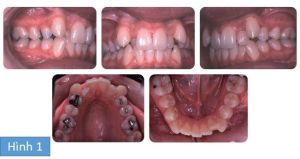

Bệnh nhân nữ 13 tuổi tới phòng khám với than phiền răng chen chúc và không hài lòng với hình dáng răng nanh của mình. Không có tiền sử bệnh lý liên quan. Cô bé có sai khớp cắn hạng I trên nền xương hạng I và kích thước dọc trung bình, phức tạp bởi chen chúc và lệch đường giữa răng.

Vì diện mạo khuôn mặt khá hài hòa nên mục đích của điều trị là không thay đổi vị trí của phần răng phía trước đáng kể, nhưng tạo ra đủ khoảng trong cung răng để giải phóng chen chúc và chỉnh sửa sai lệch đường giữa, cắn chéo răng trước và tương quan răng hàm. Ở cung hàm trên cần nhổ 2 răng tiền hàm thứ nhất và ở cung hàm dưới nhổ 2 răng tiền hàm thứ 2. Khí cụ cố định edgewise sẵn thông số hàm trên và hàm dưới được gắn và các dây Niti tròn làm thẳng ban đầu được sử dụng lèm theo laceback ở cung hàm dưới và cung hàm bên trái hàm trên.